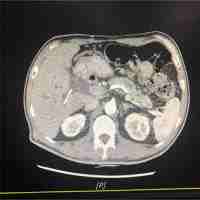

| Abstract | Pancreatic ductal adenocarcinoma (PDAC) is nearly uniformly lethal, with a median overall survival in 2014 of only 6 months. The genetic progression of sporadic PDAC (SPC) is well established, with common somatic alterations in KRAS, p16/CDKN2A, TP53, and SMAD4/DPC4. Up to 10 % of all PDAC cases occur in families with two or more affected first-degree relatives (familial pancreatic cancer, FPC), but these cases do not appear to present at an obviously earlier age of onset. This is unusual because most familial cancer syndrome patients present at a substantially younger age than that of corresponding sporadic cases. Here we collated the reported age of onset for FPC and SPC from the literature. We then used an integrated approach including whole exomic sequencing, whole genome sequencing, RNA sequencing, and high density SNP microarrays to study a cohort of FPC cell lines and corresponding germline samples. We show that the four major SPC driver genes are also consistently altered in FPC and that each of the four detection strategies was able to detect the mutations in these genes, with one exception. We conclude that FPC undergoes a similar somatic molecular pathogenesis as SPC, and that the same gene targets can be used for early detection and minimal residual disease testing in FPC patients. |